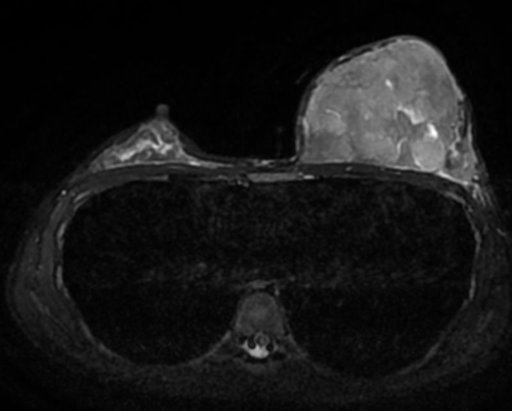

Vòng một đầy đặn thường được xem là nét đẹp nữ tính. Thế nhưng, khi sự phát triển có dấu hiệu bất thường, thiếu cân đối quá mức giữa hai bên vú thì đó có thể do sự xuất hiện của khối u đang âm thầm phát triển trong tuyến vú.